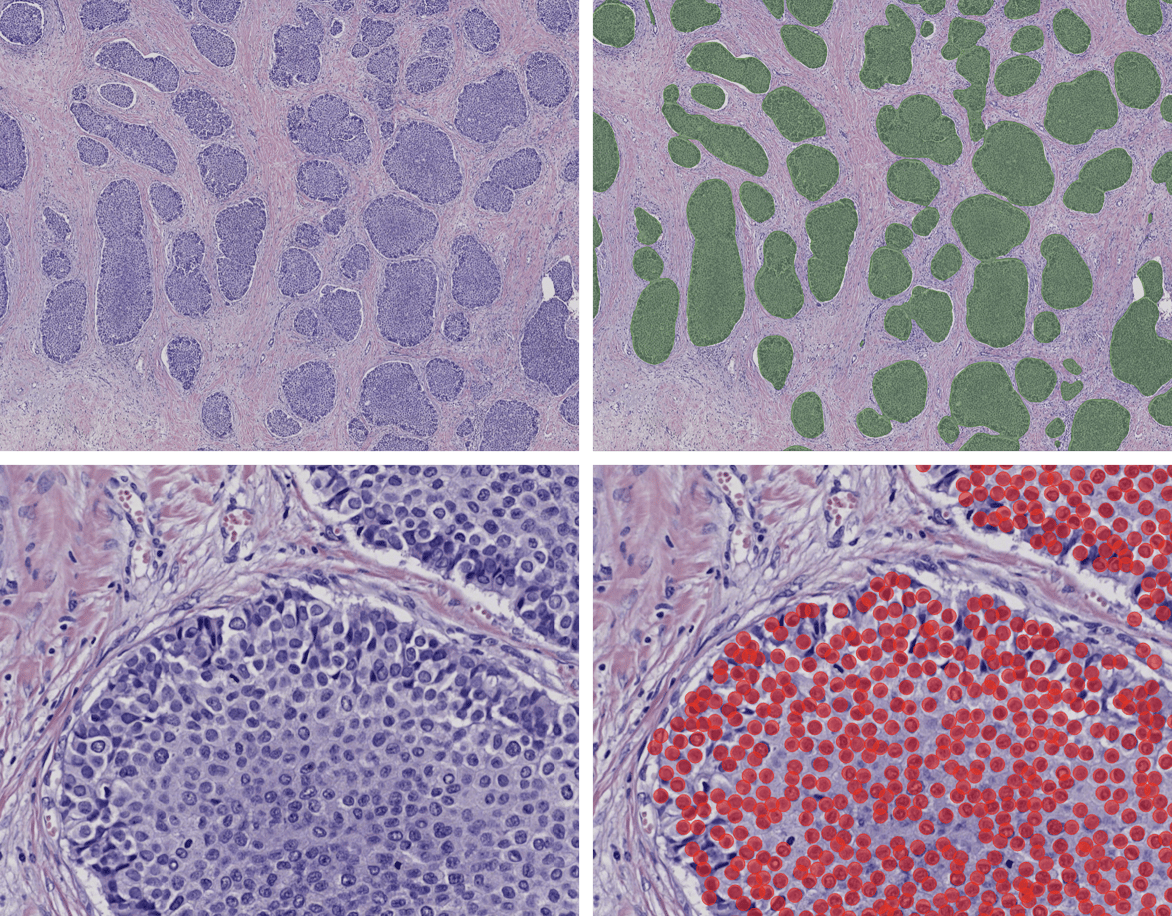

- Oncology animal model characterization and efficacy studies: AI can provide fast and accurate solutions to quantify and identify tumor and non-tumor areas, immune cells, vasculature, and invasiveness either in H&E-stained slides or immuno-stained slides.

H&E-stained section from breast cancer (left panel). The right panel showing same section analyzed by an AI algorithm that can identify and quantify tumor (green areas) vs non-tumor areas and also identify and count the numbers of neoplastic cells (red circles).